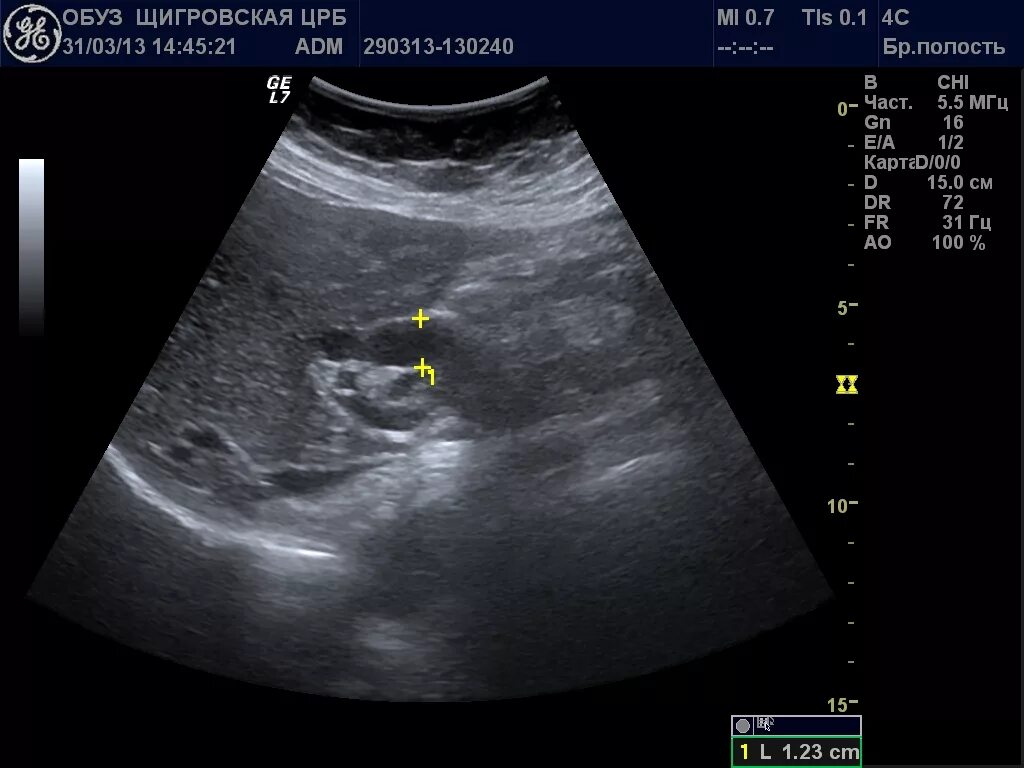

Расширен проток